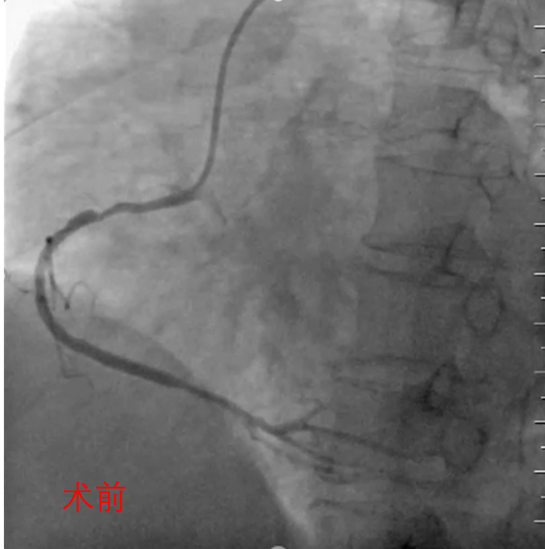

● 冠脉造影

造影提示:

•RCA近中段长病变,最重狭窄85%,远段斑块狭窄50%;

•LAD可见钙化影,中段斑块狭窄60%:

•对角支开口斑块狭窄50%,前向血流TIMI 3级;

•LCX中段斑块狭窄85%,前向血流TIMI 3级。